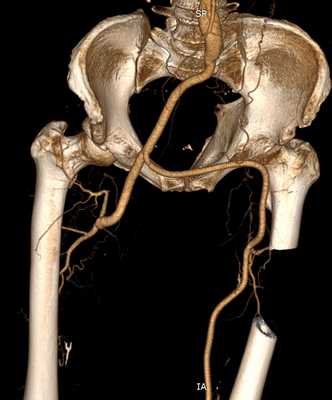

Мультиспиральная компьютерная томография проводится при наличии времени для детальной диагностики и позволяет очень точно выявить характер поражений и определить лечебную тактику.

Мультиспиральная компьютерная томография с контрастом

С целью подготовки к хирургическому лечению необходимо детально выяснить состояние артерий ноги, для этого недостаточно только УЗИ диагностики. Применяется мультиспиральная компьютерная томография с контрастом. Это исследование позволяет получить изображение сосудистого русла в трёхмерном формате и правильно спланировать хирургическое вмешательство, определиться с его видом. В нашей клинике МСКТ выполняется перед каждой реконструктивной сосудистой операцией или ангиопластикой.

- Атеросклероз сосудов нижних конечностей с поражением аорто-подвздошного сегмента. Верхний тип поражения, когда закрыты подвздошные артерии или аорта. Для данной локализации характерны боли в ягодицах при ходьбе, импотенция. Эта локализация атеросклероза опасна угрозой потери конечности. Риск ампутации составляет около 20% в год.

- Атеросклероз ног с поражением бедренно-подколенного сегмента. Закупорки наблюдаются в поверхностной и глубокой бедренной артерии. Чаще всего беспокоят боли в мышцах голени при ходьбе. Подобные поражения протекают более доброкачественно. Риск ампутации составляет не более 5% в год.